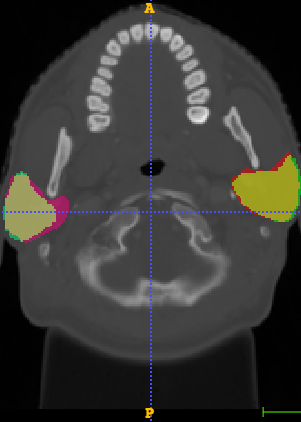

In Chapter 6, we propose an end-to-end, atlas-free 3D convolutional deep learning framework for fast and fully automated whole-volume HaN anatomy segmentation [115]. Our deep learning model, called AnatomyNet, segments OARs from head and neck CT images in an end-to-end fashion, receiving whole-volume HaN CT images as input and generating masks of all OARs of interest in one shot. AnatomyNet is built upon the popular 3D U-net architecture, but extends it in three important ways: 1) a new encoding scheme to allow auto-segmentation on whole-volume CT images instead of local patches or subsets of slices, 2) incorporating 3D squeeze-and-excitation residual blocks in encoding layers for better feature representation, and 3) a new loss function combining Dice scores and focal loss to facilitate the training of the neural model. These features are designed to address two main challenges in deep-learning-based HaN segmentation: a) segmenting small anatomies (i.e., optic chiasm and optic nerves) occupying only a few slices, and b) training with inconsistent data annotations with missing ground truth for some anatomical structures. We collect 261 HaN CT images to train AnatomyNet, and use MICCAI Head and Neck Auto Segmentation Challenge 2015 as a benchmark dataset to evaluate the performance of AnatomyNet. The objective is to segment nine anatomies: brain stem, chiasm, mandible, optic nerve left, optic nerve right, parotid gland left, parotid gland right, submandibular gland left, and submandibular gland right. Compared to previous state-of-the-art results from the MICCAI 2015 competition, AnatomyNet increases Dice similarity coefficient by 3.3% on average. AnatomyNet takes about 0.12 seconds to fully segment a head and neck CT image of dimension , significantly faster than previous methods. In addition, the model is able to process whole-volume CT images and delineate all OARs in one pass, requiring little pre- or post-processing. We demonstrate that our proposed model can improve segmentation accuracy and simplify the auto-segmentation pipeline. These contributions are released as an open-source software package called AnatomyNet, which is publicly available555https://github.com/wentaozhu/AnatomyNet-for-anatomical-segmentation. Portions of this chapter were published as part of [115].